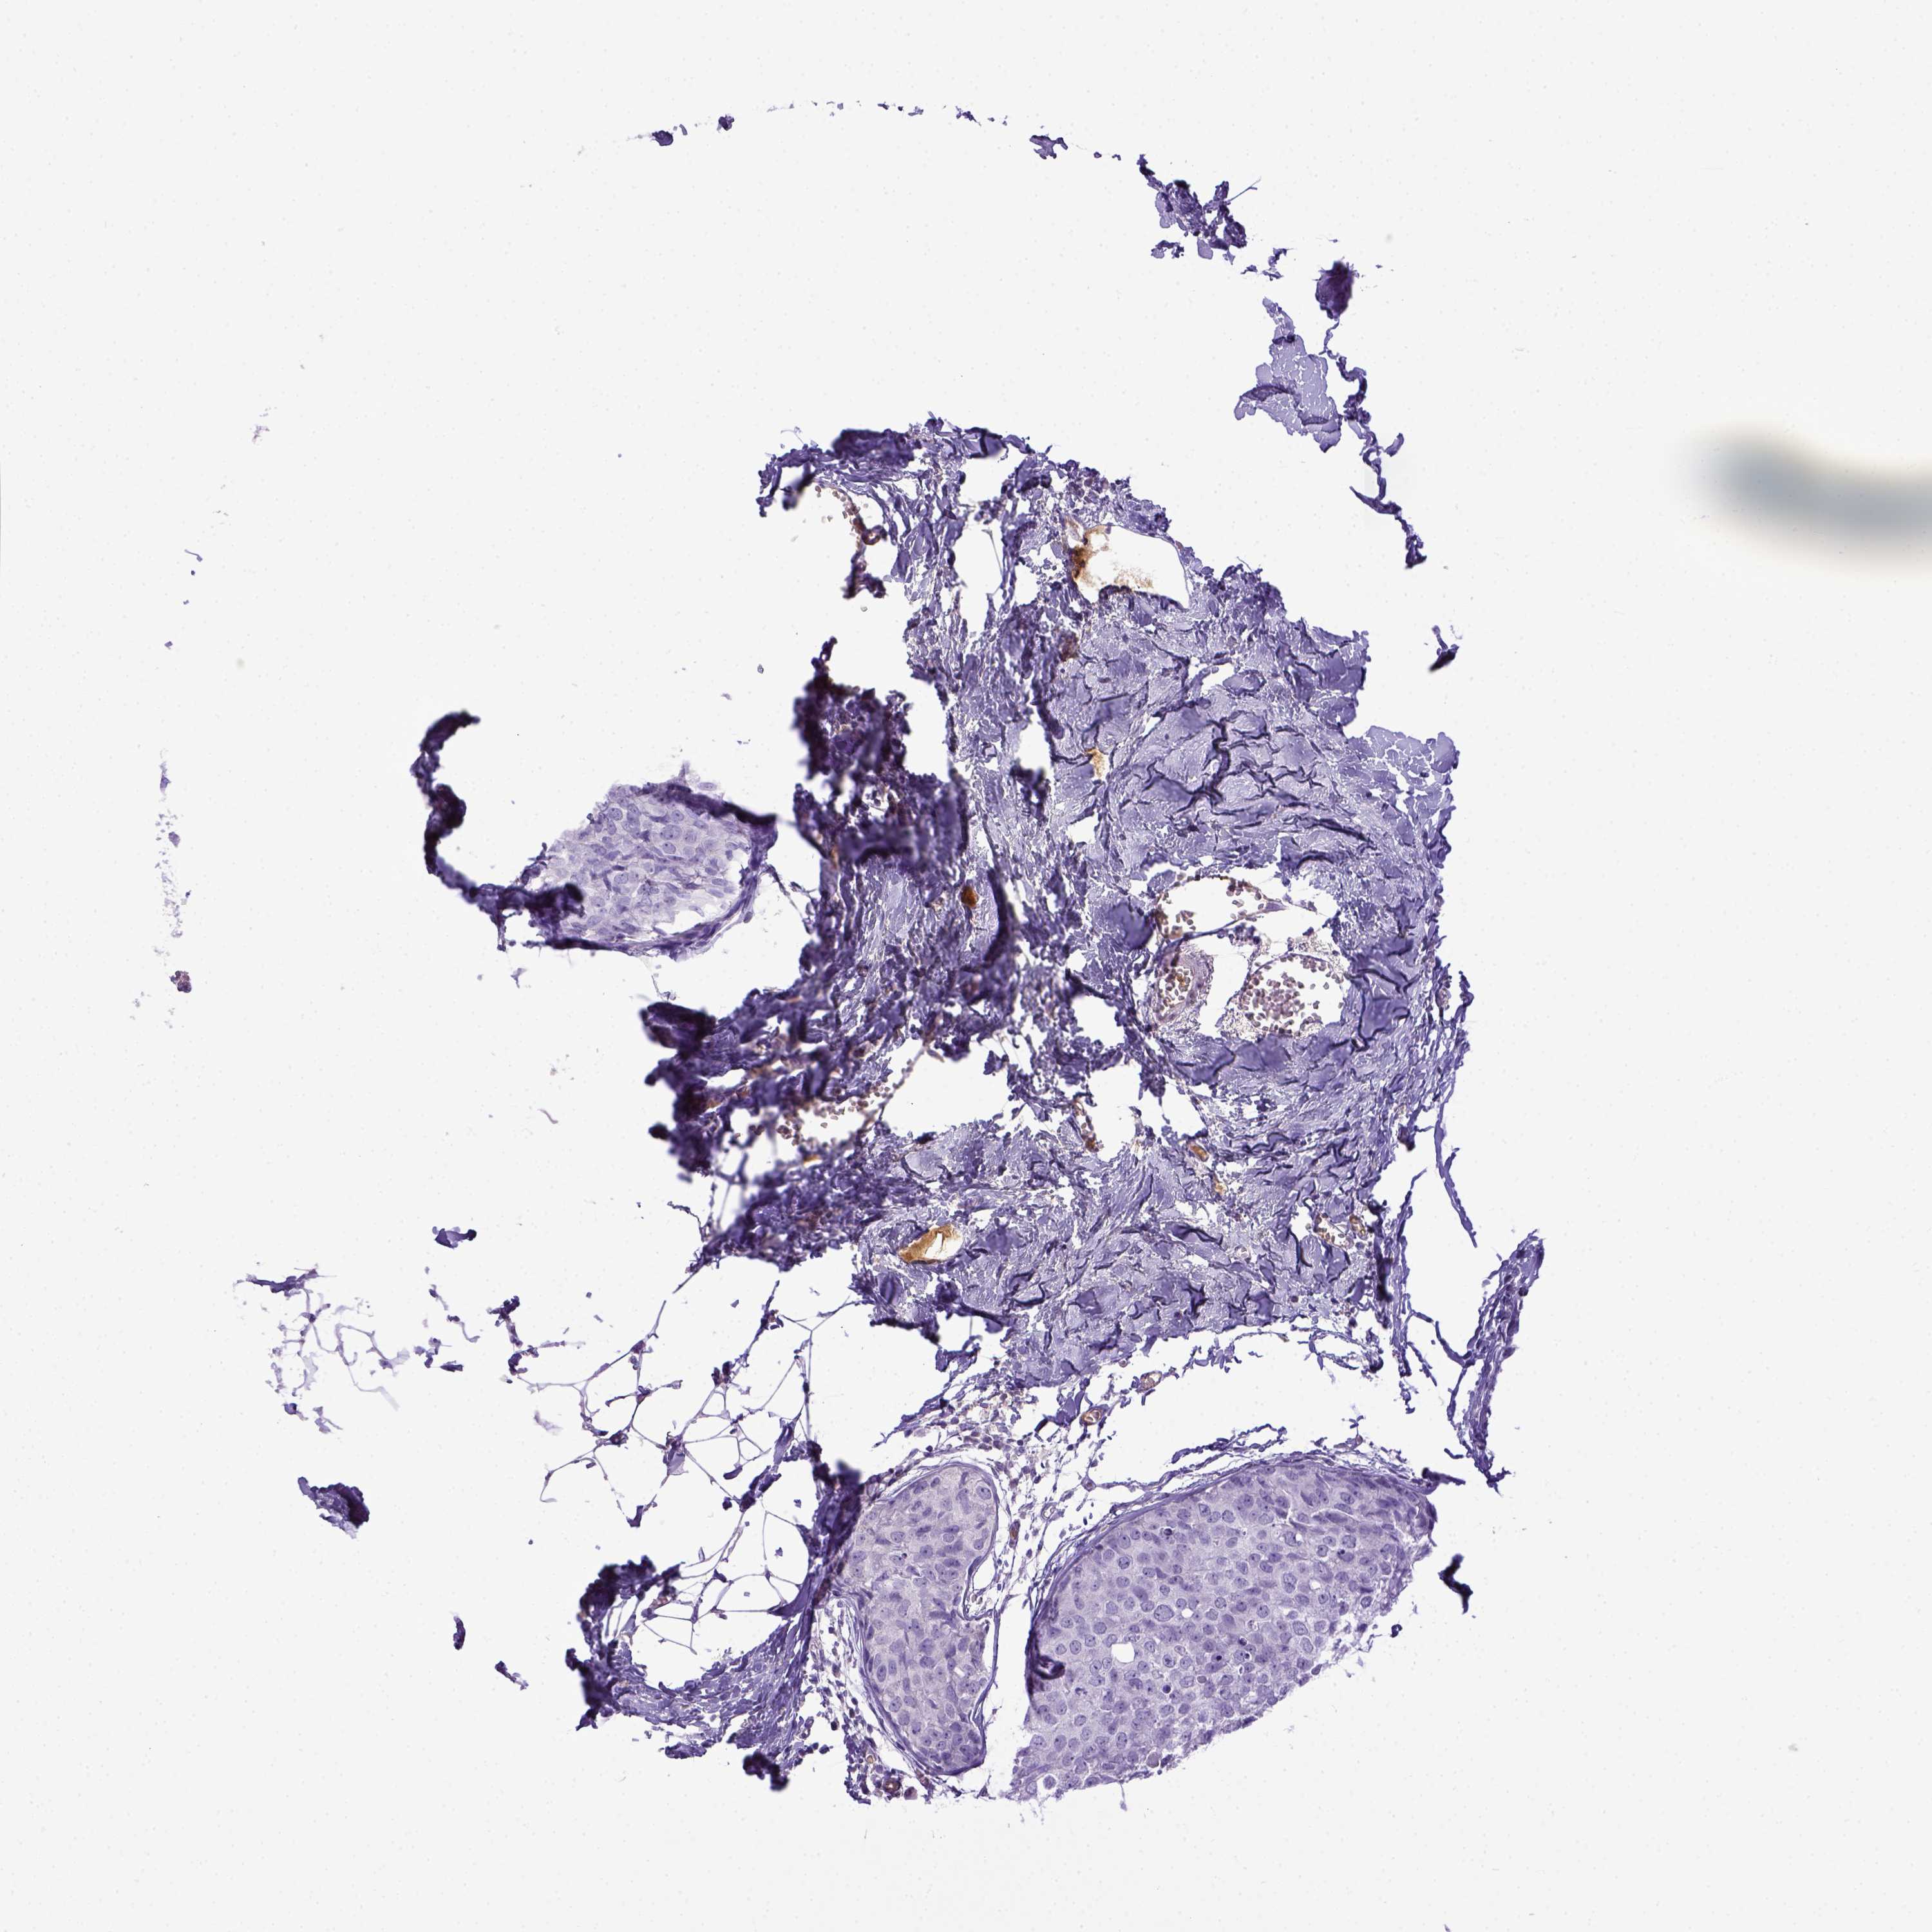

BRCA TCGA BRCA VALIDATION PROTEIN EXPRESSION

ANTIBODIES

AND

VALIDATION